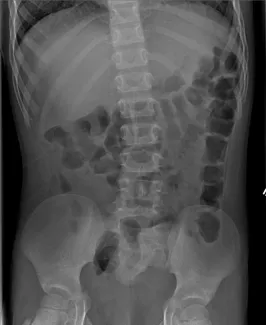

X-ray of clean colon

X-ray of constipated colon

Abdominal Xrays are necessary to evaluate the effectiveness of the laxative or enema therapy and to identify the amount of stool in the colon. These will be done at each office visit.

Also, the surgeon or surgical nurse will determine if there is hard stool by rectal exam. If found, this can be treated by enemas or suppositories, If these fail to help the stool pass, it might be necessary to disimpact the stool in the operating room, under anesthesia.

Firm bowel movements can be painful to pass. This can lead to stool with-holding which further worsens constipation. Blood streaks lining the firm stools may mean anal fissures, which are cracks or tears near the anus caused by passing hard stools. If this is noted, increase fluid intake and call our office to schedule a clinic visit and an abdominal Xray. The dose of oral laxatives may need be increased before the clinic visit.